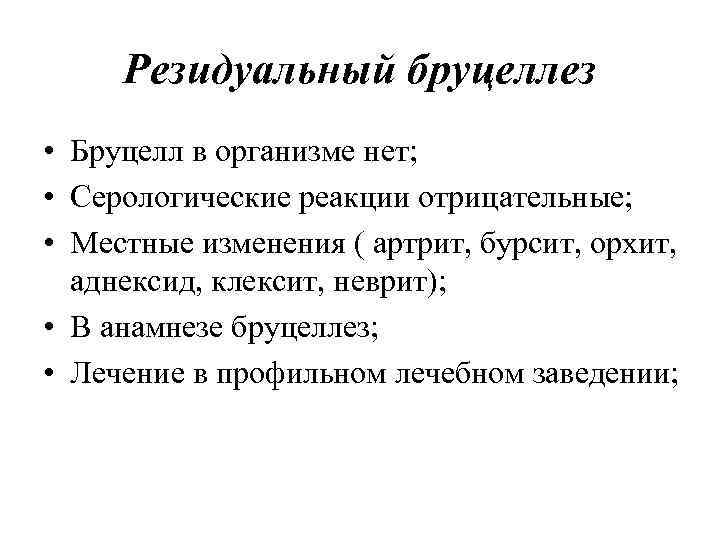

Резидуальный бруцеллез • Бруцелл в организме нет; • Серологические реакции отрицательные; • Местные изменения ( артрит, бурсит, орхит, аднексид, клексит, неврит); • В анамнезе бруцеллез; • Лечение в профильном лечебном заведении;

Резидуальный бруцеллез • Бруцелл в организме нет; • Серологические реакции отрицательные; • Местные изменения ( артрит, бурсит, орхит, аднексид, клексит, неврит); • В анамнезе бруцеллез; • Лечение в профильном лечебном заведении;